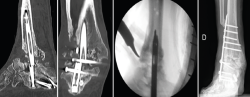

Figura 5. Imágenes de tomografía computarizada con el clavo roto. Finalización de la extracción con la guía curvada a través de la luz del clavo. Rescate con placa tibiotalocalcánea e injerto corticoesponjoso colocado en el foco.

Se reintervino al paciente realizando la extracción del fragmento distal del clavo sin dificultad. Para la extracción del fragmento proximal, se practicó, como en el caso anterior, además de la utilización de las guías curvadas, en el foco de pseudoartrosis, una muesca en el clavo con la fresa de alta velocidad para apoyar el escoplo. De ese modo, con la ayuda de la percusión directa sobre el clavo, se consiguió la extracción del extremo proximal a través de la planta del pie. Tras legrar las superficies articulares y aportar injerto tricortical de cresta ilíaca, se realizó la fijación con una placa de artrodesis TTC (Palex Medical) (Figura 5).